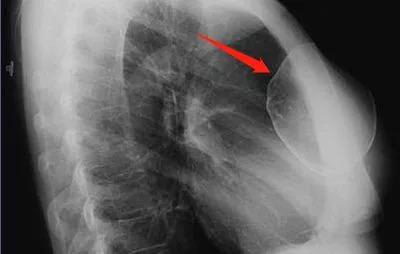

隆胸假体在X光片下的成像